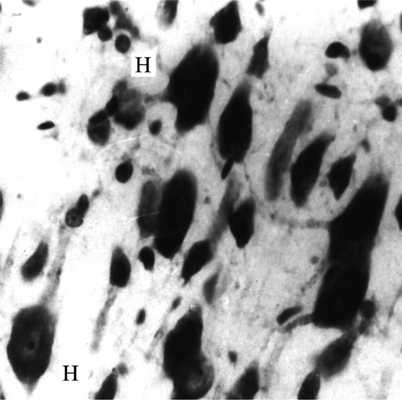

Рис. 3. СМК крысы после ДС (световая микроскопия). Нейроны в состоянии набухания (Н). Окраска по методу Ниссля. Ув. 250.